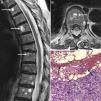

A 76-year-old female patient came to the clinic due to lumbar spine pain and weight loss, which had progressed over the past 6 months. She had been diagnosed with systemic sclerosis (SS) and interstitial lung disease 5 years prior and had been treated with cyclophosphamide induction therapy for 18 months (6 monthly cycles and 4 trimestral ones), followed by azathioprine and low dose steroid as maintenance treatment. Upon examination, the patient presented cachexia and diffuse pain on spinous process palpation. Spinal X-rays showed anterior vertebral body collapse at D8 and a magnetic resonance (MR) revealed multiple round lesions with a fluid-fluid level, with a hyperintense signal on the superior level potentiated sequence on T2 and an intermediate signal on T1, with hypointense signal on the inferior level of both sequences (Fig. 1A and B). A bone biopsy revealed that the lesions were metastasis from a poorly differentiated signet ring cell adenocarcinoma, surrounding hemorrhagic content (Fig. 1C). From an immunohistochemical point of view, the tumor cells expressed cytokeratin 7 and protein 15 of cystic disease liquid, indicating a likely breast cancer origin. However, no primary tumor was found in follow-up, which included a bilateral mastorgraphy, a craneo-cervical and thoraco-abdomino-pelvic computed tomography, a complete radionucleide bone scan, an endoscopy and a colonoscopy. The patient was treated with paclitaxel plus carboplatin, third level analgesia, zolendronate and palliative radiotherapy, remaining stable for 6 months afterward.

Dorsolumbar spine magnetic resonance showing, in sagital (A) and axial (B) projections of a T2 potentiated sequence, the presence of multiple vertebral lesions with typical fluid–fluid levels, hyperintense superiorly and hypointense inferiorly. A bone biopsy (C) revealed that these lesions corresponded to metastasis of a poorly differentiated adenocarcinoma with signet ring cells (arrowheads), surrounding a hemorrhagic content (arrows) (hematoxilin-eosin 10×).

Fluid–fluid levels may appear when substances with different densities are contained within a cystic or compartmentalized structure.1 The presence of these levels in a bone lesion suggests internal bleeding, followed by stratification of the blood components in relation to their density.1–3 These levels may be seen on X-rays or tomography, but the best detection method is MR.3 The superior level is usually hyperintense in relation to the inferior one in the T2 potentiated sequence because the latter may contain cellular components. However, in the T1 potentiated sequence the aspect varies depending on the stage of the lesion, showing an increased signal in the superior level when the hemorrhage is subacute, presumably due to the presence of extracellular metahemoglobin.4 Fluid–fluid levels have been detected in various benign bone lesions, oncluding aneurysmatic bone cysts, simple bone cysts, giant cell tumors, chondroblastoma, osteoblastoma, brown tumors, fibrous dysplasia, Langerhans’ hystiocytosis, intraosseous ganglions and hemangiomas, but also in malignant lesions such as telangiectasic osteosarcoma, the malignant fibrous hystiocytoma, fibrosarcoma, and plasmocytoma.1,3 However, these levels appear rarely in bone metastasis, with only 6 cases published up to date.2,3,5–8 In 3 of them there was a past history of cancer, breast2,5 and bladder.7 However, in the rest of the cases, the detection of fluid-fluid levels revealed the presence of neoplasia, 2 of them respiratory in origin6,8 and one unknown,3 as our patient's case. The lesions were multiple in 3 cases, all of them affecting the spine.2,3,7 Although the history of SS probably had no influence on the type of metastasis, these patients have an increased risk of neoplasia, especially lung, hematological, bladder and hepatocellular,9 with diagnosis not always easy in early stages. Another factor that must be taken into account in this case is treatment with cyclophosphamide because this drug may be associated with neoplasias such as leukemia, lymphoma, non-melanoma skin cancer and bladder neoplasia.10 In conclusion, although fluid-fluid levels are not specific, when faced with the presence of multiple vertebral lesions of this kind, it is important to consider bone metastasis among the differential diagnosis.